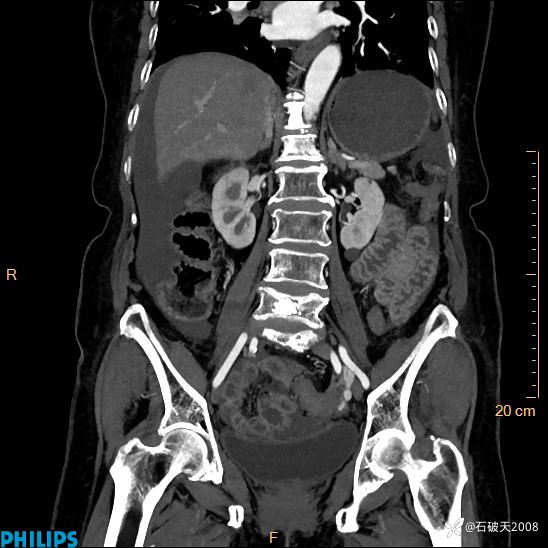

平扫